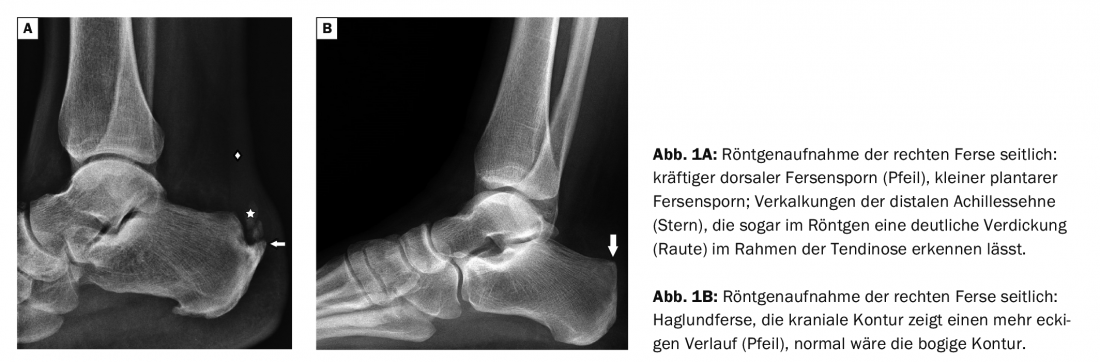

Haglundexostosis and dorsal calcaneal spur must be differentiated with regard to localization. The spur is located more caudally (Fig. 1A). The local symptomatology is about 2 to 3 cm caudal to the Achilles tendon, and the Achillodynia is about 3 to 5 cm cranial to the tendon insertion at the calcaneus. While in Haglund’s heel (Fig. 1B) a mechanical irritation of the adjacent tissue causes the discomfort, the heel spur results from excessive traction of the Achilles tendon, often as a consequence of shortening of the calf muscles.

Case report 1 shows a lateral radiograph (Fig. 1A) of a 57-year-old man with dorsal pain symptoms provocable by dorsiflexion of the foot, a powerful dorsal calcaneal spur, and a small plantar. The radiograph of a 54-year-old female patient with upper heel pain shows a Haglund’s heel with corresponding Haglund’s syndrome (Fig. 1B) . Calcification of the distal Achilles tendon suggests advanced tendinosis with chronic recurrent tendinitis. In the image examples (2A, B) in case 2. of two men aged 48 respektvie 59 years, a small dorsal calcaneal spur is delineable in each case on CT (other question, fracture exclusion), also an initial haglund exostosis (Fig. 2B) and tendinosis of the Achilles tendon. Case report 3 (Fig. 3A,B) documents MR-tomographically a considerable degeneration and tendinitis of the Achilles tendon of a 54-year-old man (long-time endurance athlete, strain after overstretching of the tendon), the small heel spur is more difficult to delimit in the MRI than in the CT.